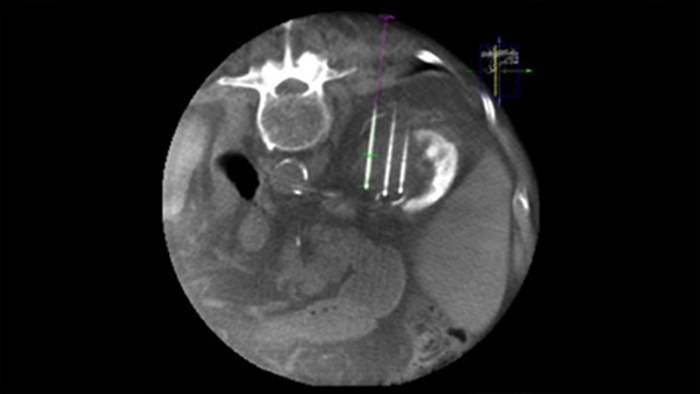

L’ablation percutanée (radiofréquence, micro-ondes et cryoablation) est un traitement peu invasif bien établi des tumeurs des reins, du foie, des poumons et des os. Il est essentiel de définir les limites de la tumeur et de décider d’un nombre optimal d’aiguilles et de la trajectoire d’aiguille correspondante afin de pouvoir effectuer un traitement complet de la tumeur sans endommager les tissus environnants. Une navigation précise à faible dose vers la lésion concernée sans repositionnement de l’aiguille augmente les chances de réussite et réduit le risque de complications de vos biopsies ou de vos ablations. La confirmation du point final du traitement d’ablation s’effectue avec l’imagerie 3D lorsque le patient est encore sur la table.

SmartCT Soft Tissue offre une technique d’acquisition CBCT (Cone Beam CT) complétée par un guidage pas à pas des outils de visualisation 3D et de mesure avancés, tous accessibles sur le module à écran tactile depuis la table.

Grâce à CBCT, faites l’acquisition d’une image CBCT après ablation pour démontrer l’étendue de la couverture tumorale et confirmer l’exhaustivité du traitement.